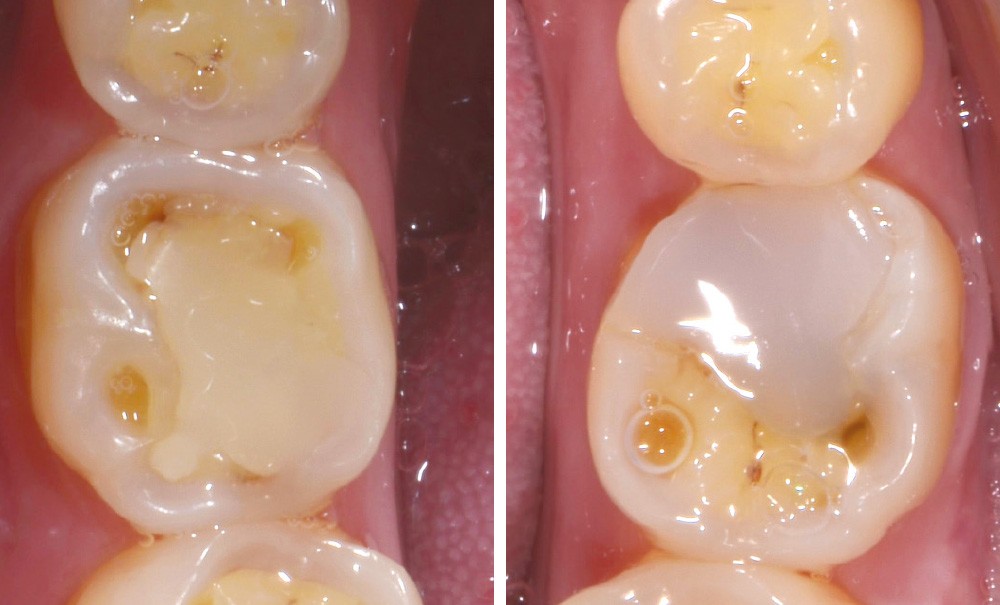

Une patiente âgée de 28 ans se présente en consultation avec une inquiétude au sujet de ses dents postérieures : elle a observé une usure avec un « jaunissement » des faces occlusales et se plaint de sensibilités répétées (fig. 1 à 3).

L’examen général met en évidence un bruxisme nocturne ainsi qu’une consommation peut-être excessive d’agrumes.